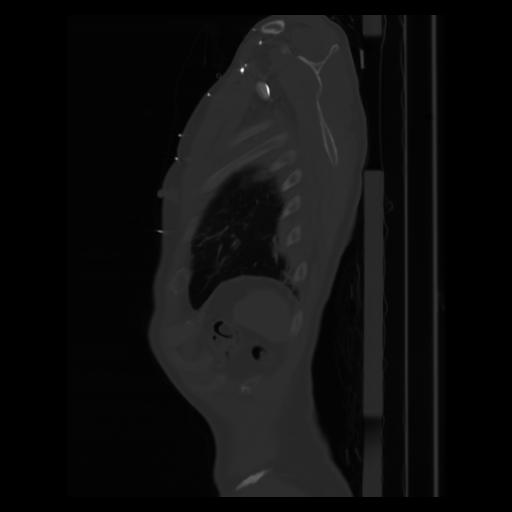

30 CUERPO,CE,Sagittal,3.000,CUERPO,Sagittal,